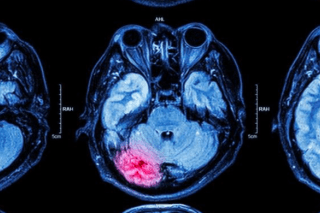

Sensibilisation à l'AVC: une journée mondiale saluée par les concernés

L’accident vasculaire cérébral concerne chaque année environ 16’000 Suisses.

Appelé aussi attaque cérébrale, ses conséquences, parfois visibles, parfois invisibles, sont souvent mal connues, au point qu’une journée mondiale de sensibilisation a été consacrée le 29 octobre à l’AVC.